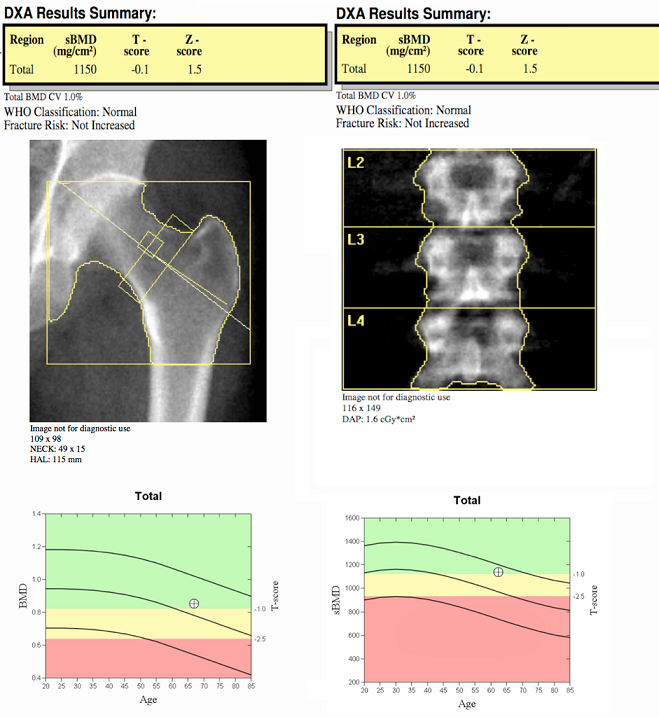

DEXA exam summary

Full-body DEXA exams are offered at our hospital imaging centers. Bone densitometry, using DEXA (dual-energy X-ray absorptiometry), safely, accurately and painlessly measures bone density and the mineral content of bone. DEXA is the most widespread, non-invasive test for the detection of osteoporosis, and is the best way to identify individuals who are at increased risk for future fractures. Based on your test results, your physician can suggest treatment options from exercise and lifestyle changes, nutritional supplements or medication. The goal of diagnosis and treatment is to prevent fractures.